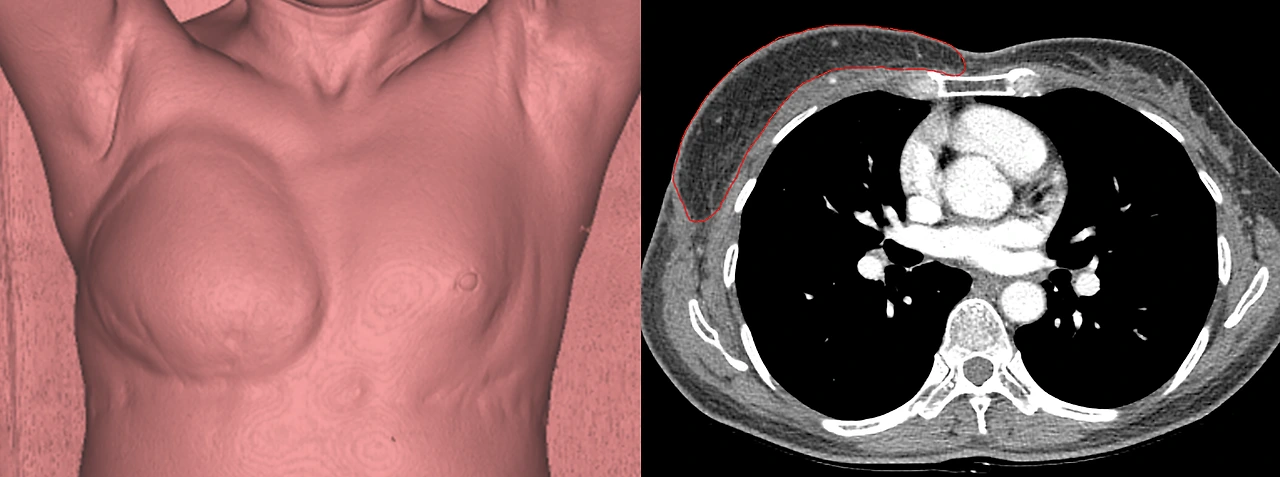

EMR 과 같이 발전한 PACS (Picture Archiving and Communicating System), 즉 의료영상 저장/전송 시스템은 의료 현장을 극적으로 변화시킨 또 다른 주인공이다. 모든 영상검사를 컴퓨터를 통해 볼 수 있게 된 이후 의료영상 데이터의 활용도는 비약적으로 증가하였다. 이전까지는 상상만 할 수 있었던 영상검사 결과의 3차원 구현 및 측량이 아무렇지도 않게 시행되고 있고, 그러한 이미지들은 주로 눈으로 바로 볼 수 있는 몸의 '바깥쪽'을 수술하는 성형외과 의사들에게도 큰 변화를 주었다. 수술 전 정확한 분석과 시뮬레이션이 가능해졌고, 수술 후의 정량적 평가 및 분석이 이루어질 수 있었으며, 이는 모두 더 좋은 수술 결과 및 환자 만족, 발전된 임상 연구로 이어졌다.

필자의 논문에서 발췌. 똑똑한 이 프로그램들은 적분을 아무렇지도 않게 해낸다.